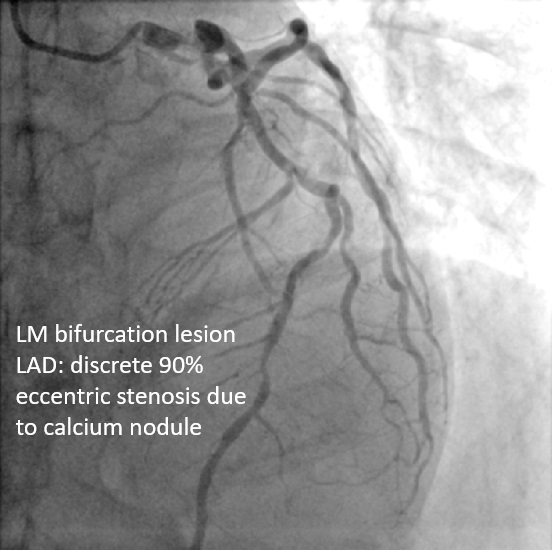

Cath report from referring hospital-LM:bifurcation lesions (1,1,1 type; 90%, 90%, 30% stenosis)-LAD:Diffuse lesions with acute bends-LCX:Severe AS changes with discrete 95% due to eccentric plaque at proximal LAD-RCA:Long CTO lesion

PCI was performed via a right femoral 7 Fr EBU 3.0 guide. LCX wiring was extremely challenging due to a large ostial aneurysm and discrete stenosis; reverse wiring failed, so the LAD was treated first. Using a Caravel microcatheter, an extra-support Rotawire was advanced, and sequential 1.25 mm and 1.75 mm burr atherectomy was done for LAD and LM–LAD segments. A 2.0 mm burr was avoided due to iliac angulation. After adequate LAD preparation, LCX wiring succeeded with a Suoh 03 wire, exchanged for a Rota Extra Support wire via Caravel. LM–LCX ostium was ablated with 1.25 and 1.75 mm burrs, though the burr could not enter LCX proper.

Suboptimal balloon dilation led to implantation of a 2.75 ¡¿ 8 mm Onyx DES at the LCX ostium. The LAD was predilated and treated with 2.0 ¡¿ 38 mm and 2.5 ¡¿ 38 mm Xience Sierra stents plus a 3.5 ¡¿ 15 mm Megatron for LM–LAD. IVUS confirmed full stent expansion and apposition with no residual stenosis. A minor LAD ostial type II dissection was observed but without flow limitation.